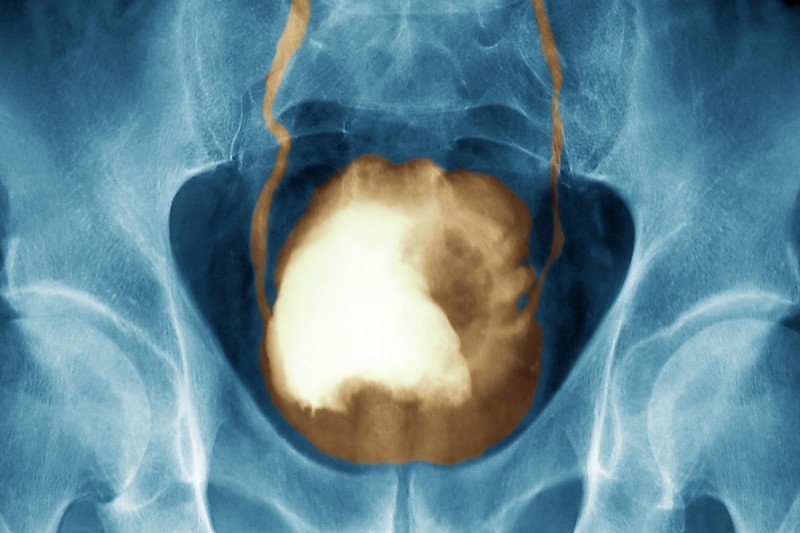

x-ray of bladder with large tumor